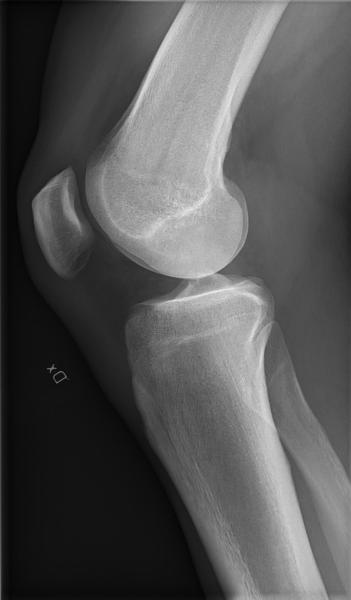

Strong, healthy bones require good structure, adequate mineral density, and good-quality bone tissue. Until recently, bone health could be assessed only through indirect imaging methods like bone-density scans, which use a small dose of ionizing radiation to produce images of bones inside the body — usually the lower (lumbar) spine and hips — to measure bone loss. It is the most common method for diagnosing osteoporosis, which reflects an individual’s risk for developing osteoporotic fractures.

However, although bone-density scans measure the amount of bone tissue, they do not provide information about how well the tissue is functioning or the quality of the tissue material. Other imaging techniques, such as CT or MRI scans, offer insight into the structure but fail to quantify tissue function and quality.